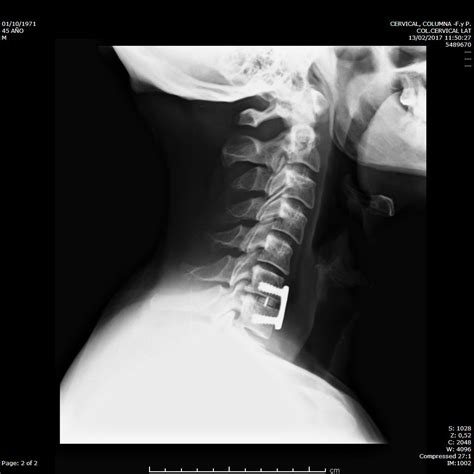

Diagnosing Hernia Discal Lumbar

Diagnosing a Hernia Discal Lumbar typically involves a combination of medical history, physical examination, and diagnostic tests. The diagnostic process may include:

• Imaging tests: Diagnostic imaging, such as X-rays, MRI, or CT scans, can help visualize the spinal discs and identify any herniations or nerve compressions.

• Spinal fusion: A procedure to join two or more vertebrae together, stabilizing the spine and reducing pain.